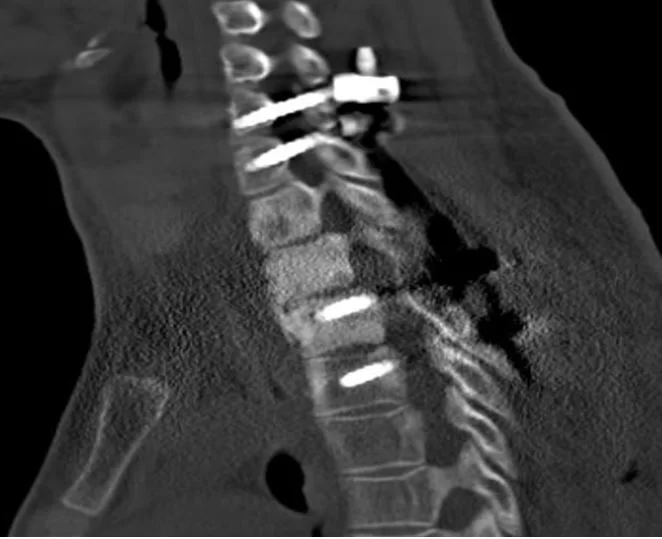

Διενεργήθη ολική αφαίρεση της βλάβης και στήριξη της αυχενοθωρακικής μοίρας της σπονδυλικής στήλης με διαυχενικές βίδες Α6-Α7-Θ3-Θ4.

Μετεγχειρητική Αξονική Τομογραφία

Τα οστεοβλαστώματα της σπονδυλικής στήλης είναι σχετικά σπάνιοι καλοήθεις όγκοι. Μπορεί όμως να προκαλέσουν σημαντική καταστροφή των φυσιολογικών ιστών ενώ ταυτόχρονα δημιουργούν μάζες οι οποίες μπορεί να πιέσουν το νωτιαίο μυελό. Η θεραπεία είναι η χειρουργική αφαίρεση του όγκου, η οποία όμως πρέπει να είναι ολική προκειμένω ο όγκος να μην υποτροπιάσει (επανεμφανισθεί). Στην προκειμένη περίπτωση κάναμε ακριβώς αυτό, μια ριζική αφαίρεση της βλάβης με στήριξη της σπονδυλικής στήλης στο ίδιο χειρουργείο. Η διεγχειρητική 3D-νευροπλοήγηση βοηθά να μπούν οι βίδες με εξαιρετική ακρίβεια.